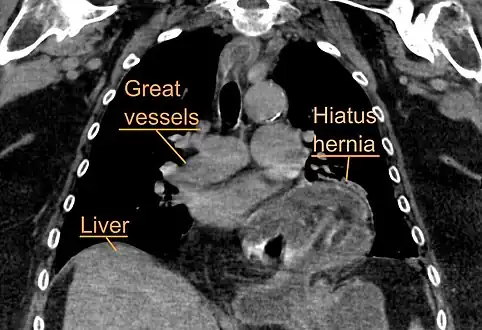

The diagnosis of a hiatal hernia is typically made through an upper GI series, endoscopy, high resolution manometry, esophageal pH monitoring, and computed tomography (CT). Barium swallow as in upper GI series allows the size, location, stricture, stenosis of oesophagus to be seen. It can also evaluate the oesophageal movements. Endoscopy can analyse the esophageal internal surface for erosions, ulcers, and tumours.

Meanwhile, manometry can determine the integrity of esophageal movements, and the presence of esophageal achalasia. pH testings allows the quantitative analysis of acid reflux episodes. CT scan is useful in diagnosing complications of hiatal hernia such as gastric volvulus, perforation, pneumoperitoneum, and pneumomediastinum.[8]

A hiatal hernia as seen on CT

A large hiatal hernia as seen on CT imaging

A large hiatal hernia as seen on CT imaging- As seen on ultrasound[9]